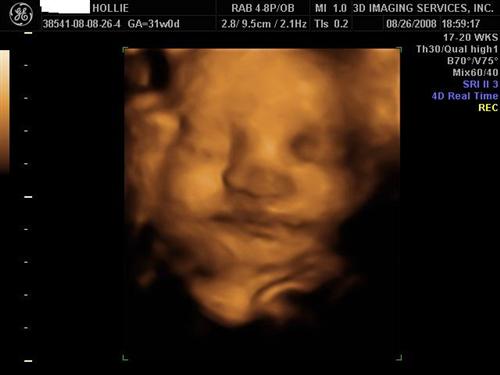

30 weeks :) super clear and adorable.

Logan's 3D pics!